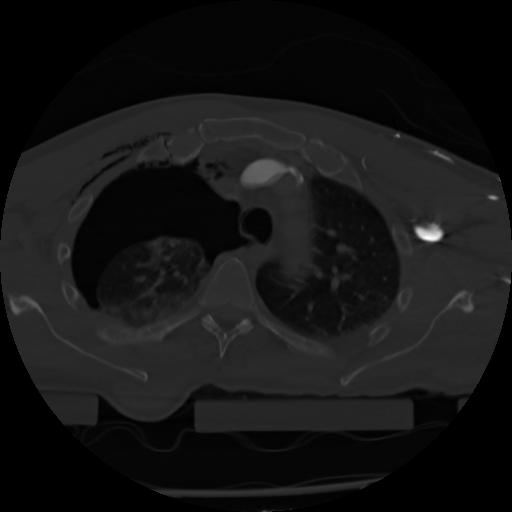

21 ANGIO,CE,Axial,3.0,ANGIO,,